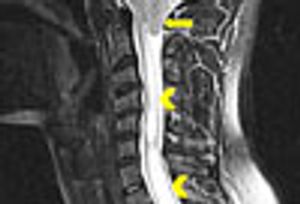

A 4-year history of headache and severe neck pain led to a diagnosis of Chiari I malformation in this patient. Here: symptoms, diagnostic tests, and treatment approaches.